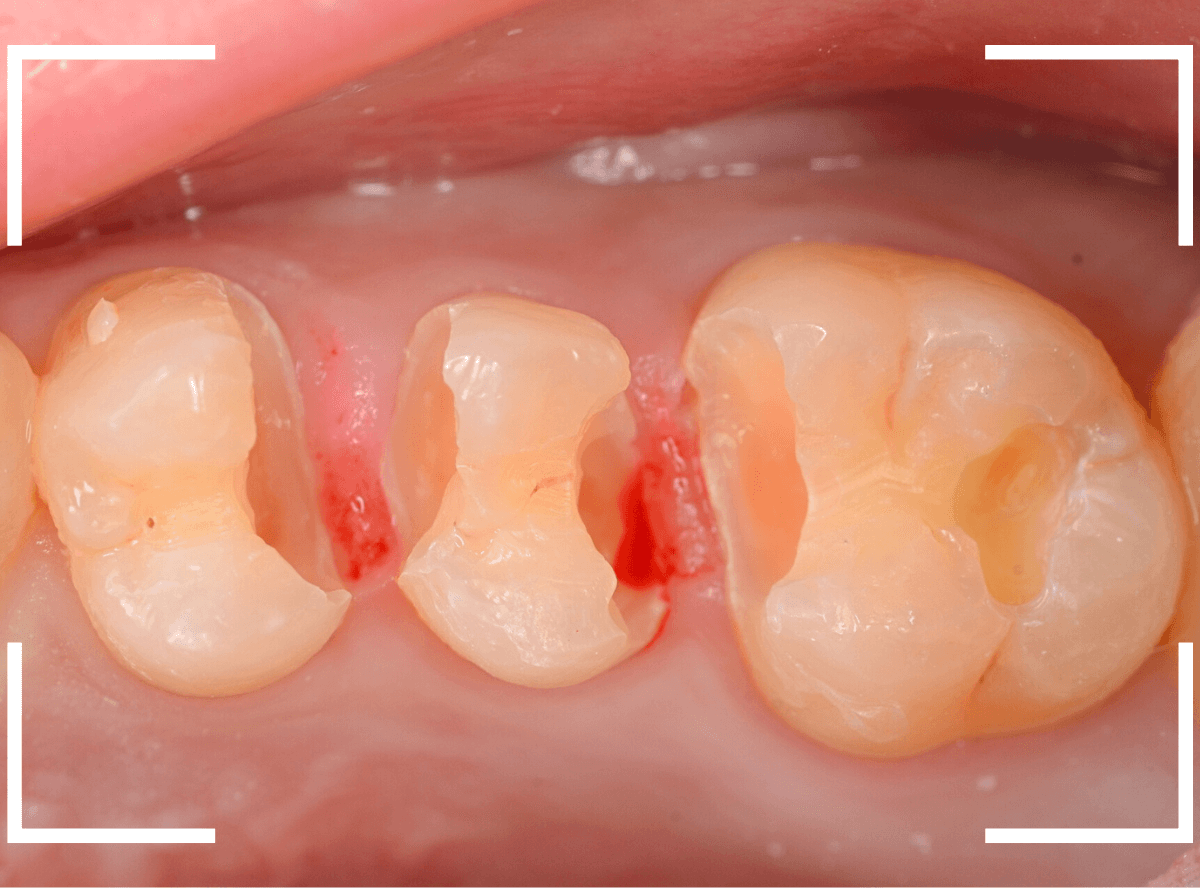

Case.17 歯の側面のレジンの中のわかりづらい虫歯

検診で、金属のつめ物のの中と、歯の側面に虫歯が見つかった方です。

まずは、手前(左)側の治療です。

こちらが、お口の中を見たところです。

〇部の中に虫歯があると思われます。

今回のように、金属のつめ物やレジン治療をしてある歯の側面の虫歯の診断はわかりづらく、難しいです。

赤く染まっている部分が虫歯です。

真っ赤ですね(^^;)

慎重に虫歯を除去していきましたが、まだ薄く染まっています。

もう少し除去する必要があります。